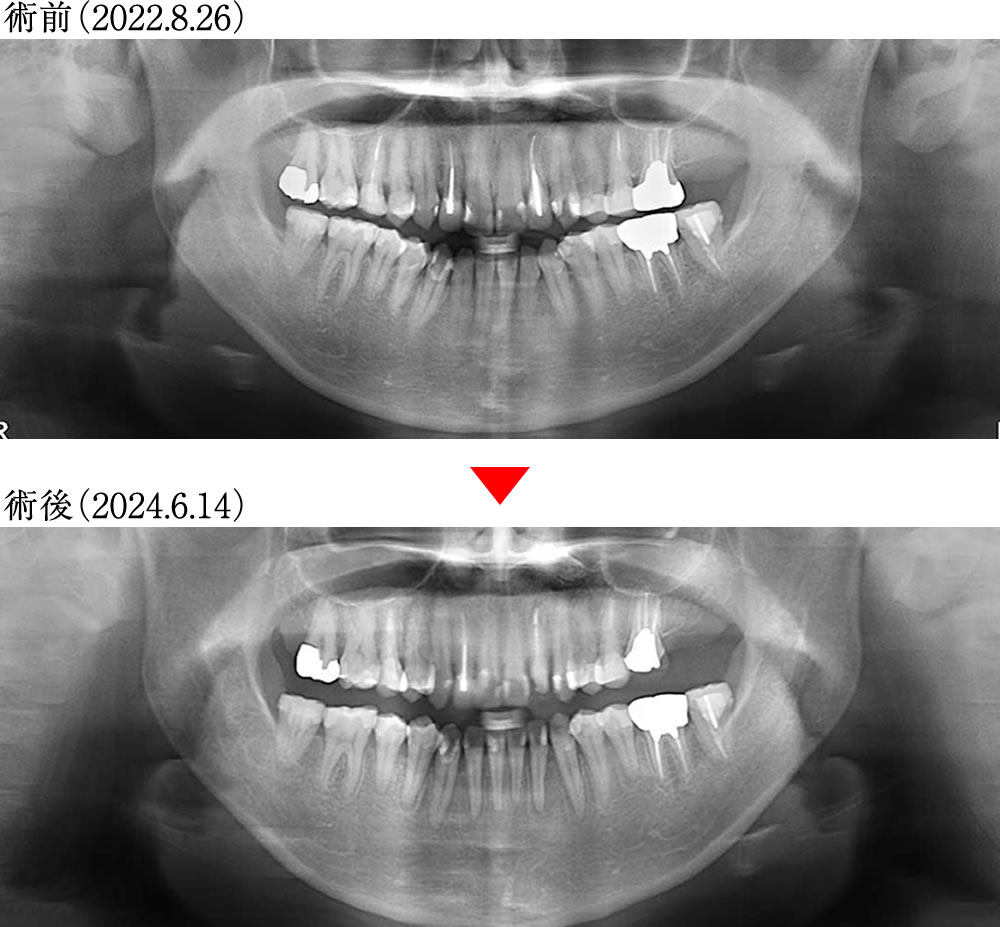

治療前後のレントゲン画像

歯軸が整直して安定した環境になりました。